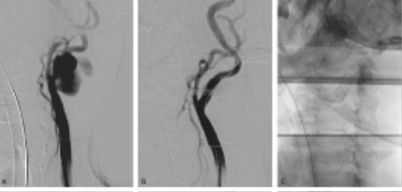

By the 5th month of follow-up, the patient was re-admitted with a recurrence of the cervical pulsatile mass. While the analytical study showed no elevation of inflammatory parameters (Leukocytes 8.71x10 with 47% neutrophils) and a C-reactive protein level of 8 mg/L, the CT scan showed apparent proximal migration of the stent graft with rupture at the caudal (common carotid) edge, Figure 5.

A) computed tomography angiography showing proximal stent graft migration and contrast leak from the distal, external carotid artery occluded with a plug (yellow arrow); B) angiogram showing contrast leak from the distal of the stent graft; C) and D) intraoperative images of the rupture exclusion through distal extension with an 8x50 stent graft.

The new rupture was corrected with an extension with an 8x50 Viabahn® stent graft through a transcervical approach. According to the previous antibiogram, the patient initiated antibiotic therapy with piperacillin-tazobactam at admission. Blood cultures were collected at admission, and they were negative after 48 hours of antibiotics. As the patient was considered high-risk for surgical approach for stent graft explant, it was decided to maintain lifelong antibiotic therapy. However, the patient evolved with nosocomial pneumonia with multiorgan failure, culminating in death on the 7th postoperative day.